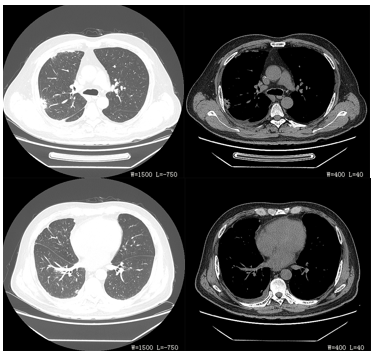

停CRRT,入院后共进行7次CRRT(模式均为CVVHDF),共53小时。停亚胺培南西司他丁(疗程9天),继续莫西沙星0.4g治疗。7月10日患者精神状态、睡眠、饮食均恢复,偶有干咳,无气短,无发热,不吸氧状态下监测血氧饱和度为95%。查体双肺未闻及干湿啰音。复查血常规、肾功、酶学(CK、CK-MB、LDH、HBDH、AST)、电解质、CRP、PCT均为正常,停用莫西沙星治疗(疗程21天)。7月15日查胸CT示右肺见索条高密度影,右侧胸腔后部见弧形水样密度影(图9-3A、9-3B、9-3C、9-3D)。患者好转出院。

图9-3A、9-3B、9-3C、9-3D 2015-7-15胸CT 右肺见索条高密度影,右侧胸腔后部可见弧形水样密度影